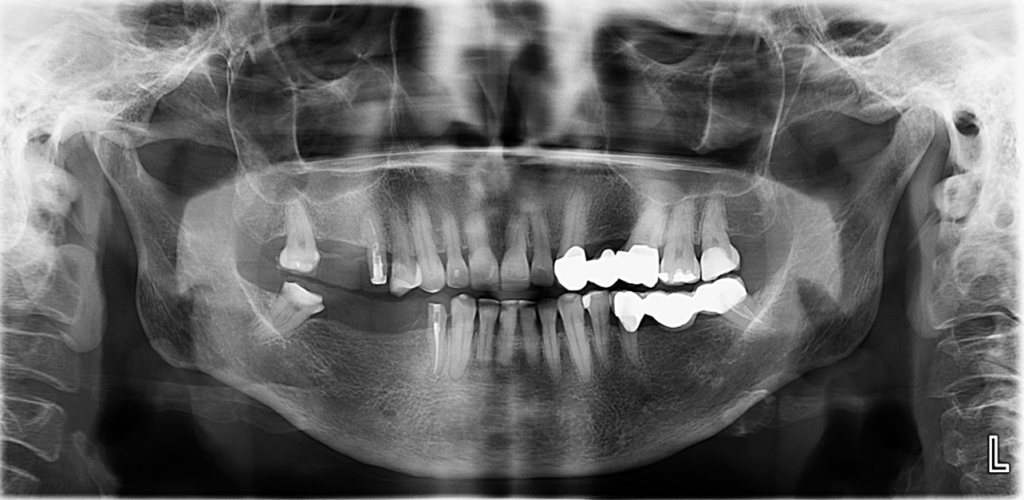

En la radiografía panorámica (Figura 1), se observa neumatización de senos maxilares con engrosamiento de la mucosa en lado izquierdo, edentulismo parcial, múltiples restauraciones coronarias y protésicas.

Radiografia Panorámica